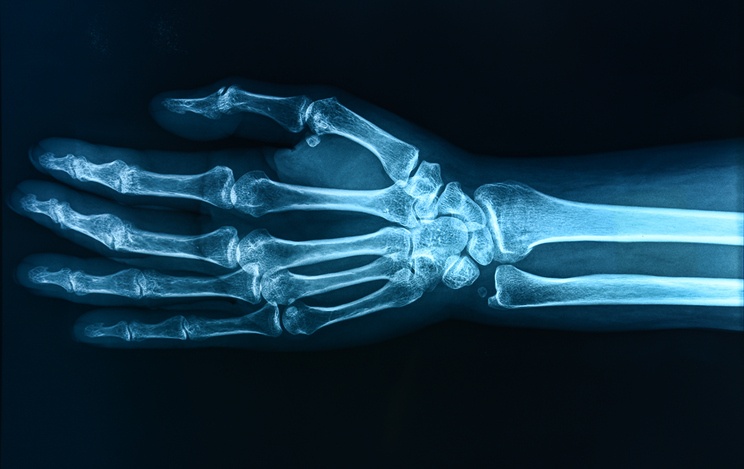

Before starting work with us, he obtained his Doctor of Medicine degree from State University of New York and did his residency at Fletcher Allen Health Care in Vermont and completed a Fellowship in MRI at the University of Rochester. Dr. Sherman is a highly specialized Doctor with training in multiple areas including Musculoskeletal Imaging.

Having radiologists, and further more — specialized radiologists on-site is a great advantage for patients as they are better image-readers (purely based on experience) than primary care physicians. He said, “General Radiologists are specialist physicians. Fellowship trained Radiologists, of which all in my group are, have additional sub-specialty training of 1-2 years. During the extra fellowship year(s) it’s all in one modality or specialty area of radiology.”

There is a true night and day difference between a primary care doctor reading images and a radiologist reading images. Dr, Sherman said, “This is the result of residency training programs and what they are designed to train people to do. For example all radiologists do during their residency training (1 year internship plus four years of radiology) is train to interpret images. PCPs are trained to provide clinical care to patients in both the hospital and office setting which in many if not most cases does not include formal radiology training. There is often some form of integrated teaching of radiology, which may be on what exams to order or reviewing some common radiology exams, but there is no formalized training in these types of training programs on image interpretation of the sort that radiologists receive. Thus, this creates the huge difference in the ability to read images quickly, accurately and efficiently, which allows people to take care of their patient better.”